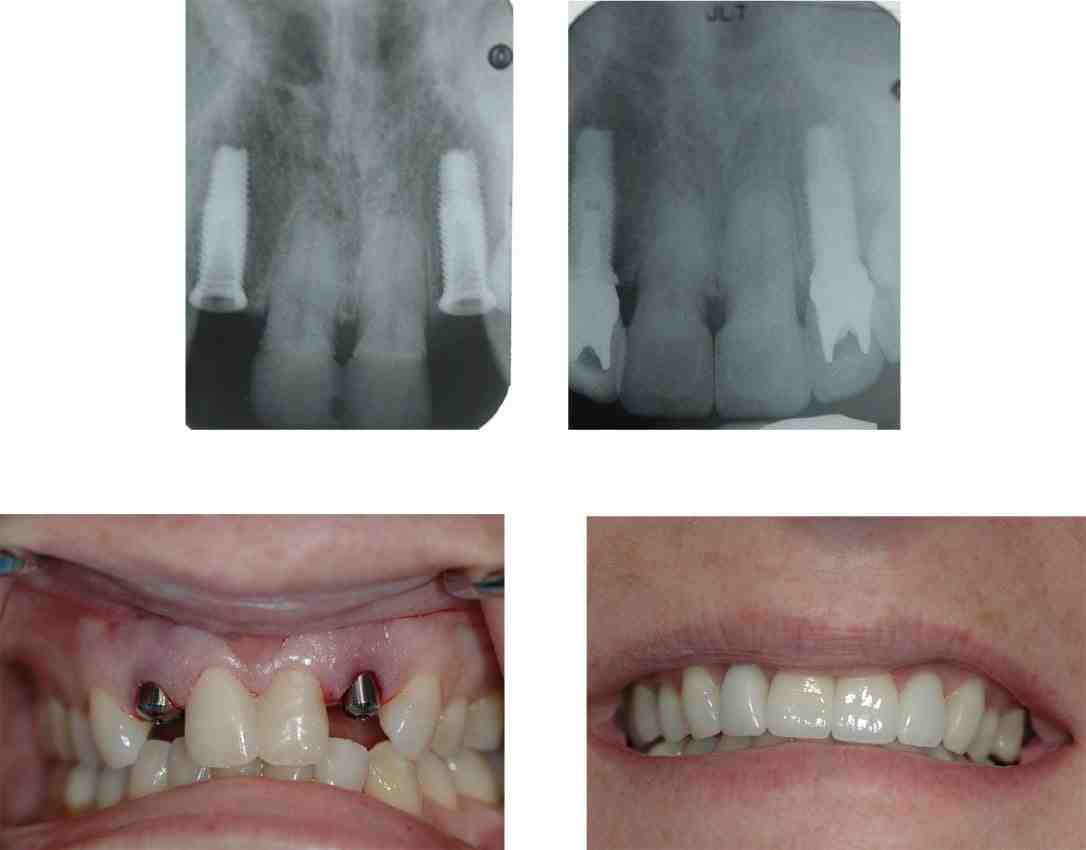

Are teeth implants painful?

Dental implants are considered the best options to replace missing or damaged teeth. The procedure itself is not painful as it is performed under general or local anesthesia to completely numb the mouth. After dental implantation, once the numbness subsides, the patient may notice mild pain.

A dental implant can help maintain a healthy bite, keep teeth in their proper place, and help decrease bone decay. The pressure and stimulation of chewing can also help preserve the jaw. Dental implants can also be beneficial to the overall beauty of your teeth.

Why dental implants are bad?

Dental implants have a high success rate of around 95% and lead to a better quality of life for many people. However, dental implants can cause complications, such as infections, receding gums, and nerve and tissue damage.